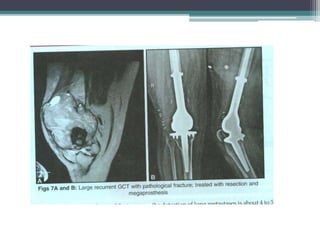

Recurrence is treated with en bloc excision.

En bloc excision is also indicated if the tumour has eroded

the cortex and extended into the soft tissues.